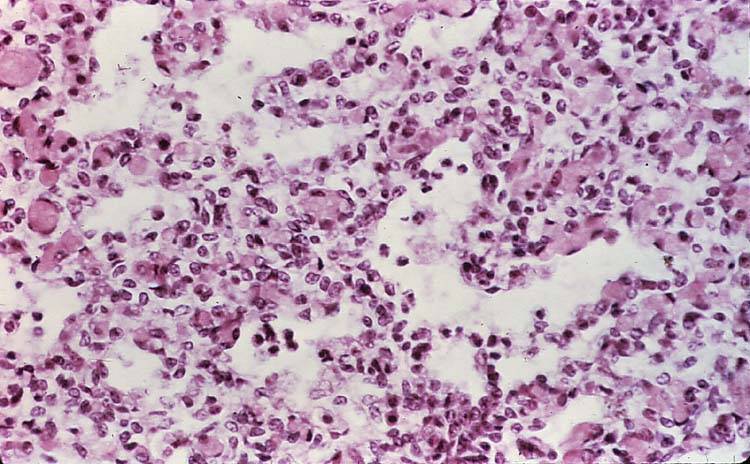

Taken from a fetal lung of a sheep.

Name the predominant cell type seen in this slide (within the alveoli).

Neutrophils